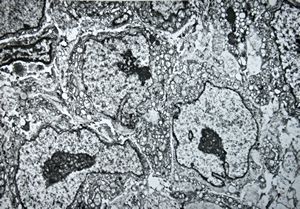

M, 62y. | angiomatous tumor, v.s. Kaposi sarcoma